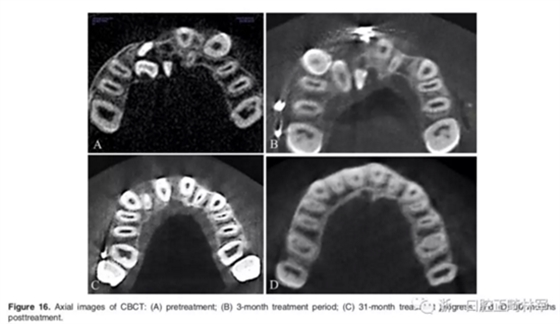

影像學:頭顱側位片示:矢狀向和垂直向骨骼發(fā)生變化(ANB角,3°;SN-MP,51°);上頜切牙略前傾(U1-SN,106°),與下頜切牙一致(IMPA,75°);病人的面部輪廓得以保持。全景片示:由于牙齒萌出,上前牙區(qū)垂直向牙槽骨水平增加;雖然前牙牙根較彎曲,但其平行度仍可,且無明顯的牙根吸收。CBCT示:前牙唇側骨質連續(xù)性改善,牙根唇側支持組織變好,牙槽骨高度、厚度均有增加,但轉矩的改變一定程度上導致了局部應力的增大。

2年隨訪:咬合關系保持穩(wěn)定,無明顯復發(fā),下頜有一定晚期生長趨勢;前牙牙齦外形、牙冠高度無明顯變化;唇側牙槽骨高度、厚度均保持良好。